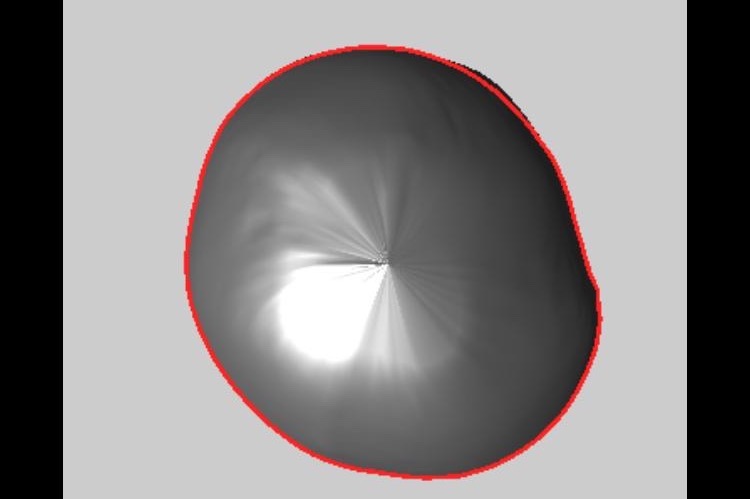

We have been for a consultation at a clinic called Technology in Motion who specialise in Plagiocephaly and Brachycephaly in babies- Oliver unfortunately has both of these.

Oliver was born with Torticollis which basically restricted his movement and he was unable to move his neck to the right he therefore lay his head to the left causing a flat head and facial deformity.